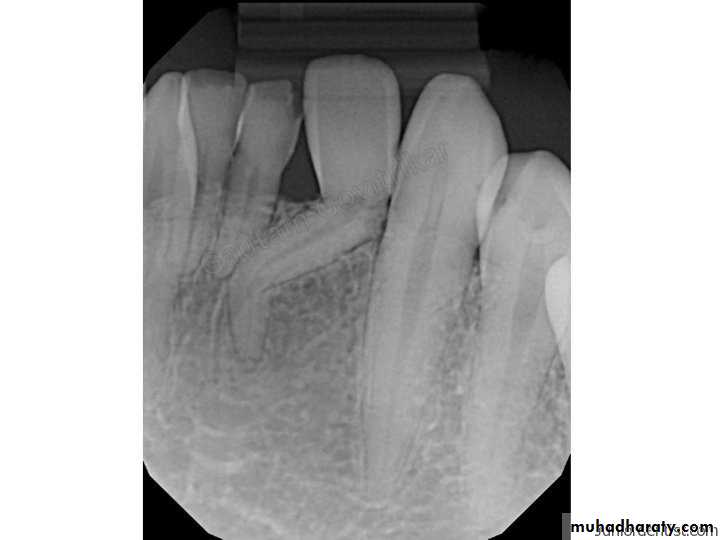

Dilaceration

Dilaceration: Is a developmental disturbance in shape of teeth. It refers to an angulation, or a sharp bend or curve, in the root or crown of a formed tooth.Etiology: The condition is thought to be due to trauma or possibly a delay in tooth eruption relative to bone remodeling gradients during the period in which tooth is forming. Developmental disturbances,

Treatment and prognosis

• Extraction of primary deciduous teeth, if they demonstrate undesired resorption and result in delayed eruption.• Grossly deformed teeth required surgical extraction because of extensive deformation of the affected tooth, repositioning and perforation of buccal alveolar ridge by the mispositioned root.

• In mild dilaceration cases, no treatment is required.